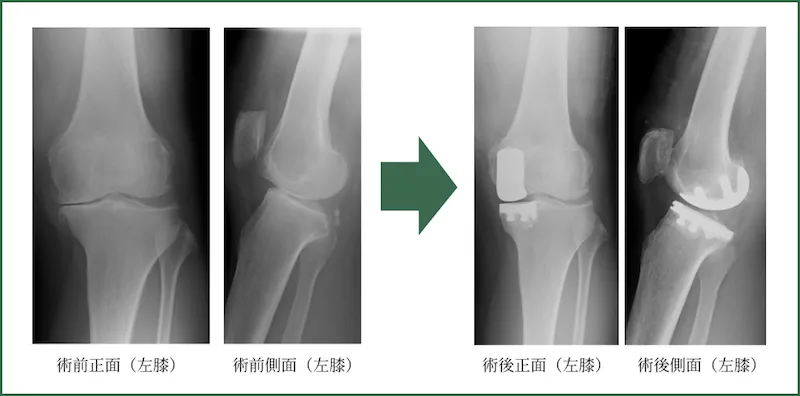

人工膝関節置換術

(Total knee arthroplasty/ Unicompartmental knee arthroplasty)

全身シールド装置(サージカルヘルメット)を使用して、感染については十分にケアして行っております。また両側症例については両側を一期的に行います。

入院期間は、両側も片側も差はなく約2週間です。退院の目安は、階段昇降が自立しておりT字杖歩行が可能な状態です。要するに自分の身のまわりのことができる状態です。術後1ヵ月程度は2回/週、術後4ヵ月程度は1回/週、それ以降、状態に応じて隔週ごと、月ごとのリハビリ通院を要します。スポーツについては、ジョギングやマラソン以外は許容しております。実際、テニス、卓球、バドミントン、登山など行っている方は多いです。よく患者さんに「どのくらいもちますか?」と聞かれることがありますが、我々の行った手術で今の所壊れてしまった(緩くなった)膝は1例もありませんので、「何とも言えないですが20~30年はもつでしょう」とお伝えしております。

よく患者さんに「どのくらいもちますか?」と聞かれることがありますが、我々の行った手術で今の所壊れてしまった(緩くなった)膝は1例もありませんので、「何とも言えないですが20~30年はもつでしょう」とお伝えしております。